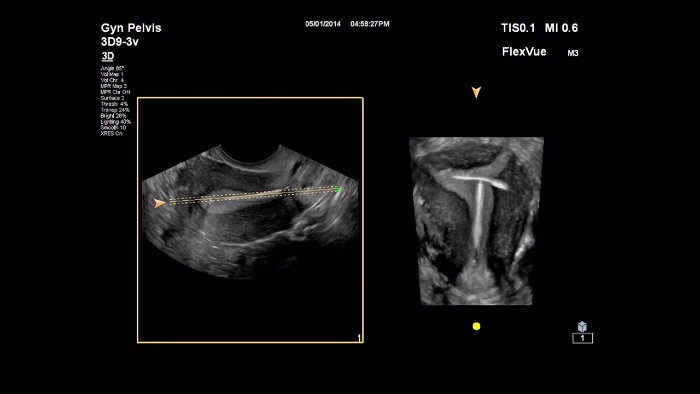

In this video Dr. Michael Ruma presents FlexVue and RexVue Volume, Philips advanced 3D evaluation tools. FlexVue and Flexvue Volume allows for easy visualization of technically difficult anatomical views from 3D volumes that are essential for diagnosis of OB/GYN pathology

In this video Dr. Michael Ruma presents FlexVue and Orthogonal View, Philips advanced 3D evaluation tools on clinical cases for OB and GYN.